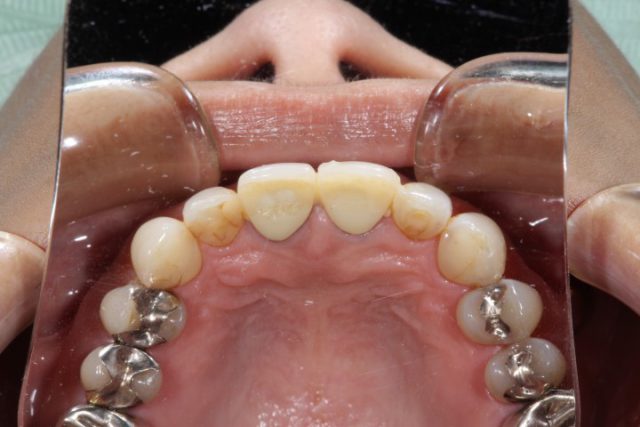

施術前

施術前の画像を見るとそれほど変色している印象を受けることはありませんが、よく見ると前歯の虫歯治療した後の部分の詰め物の変色しています。今回の患者様はこの部分をとても気にされていました。

詰め物を削りやり直したとしてもまた数年後には同じことになるため今回は思い切ってオールセラミックによる施術を選択されました。